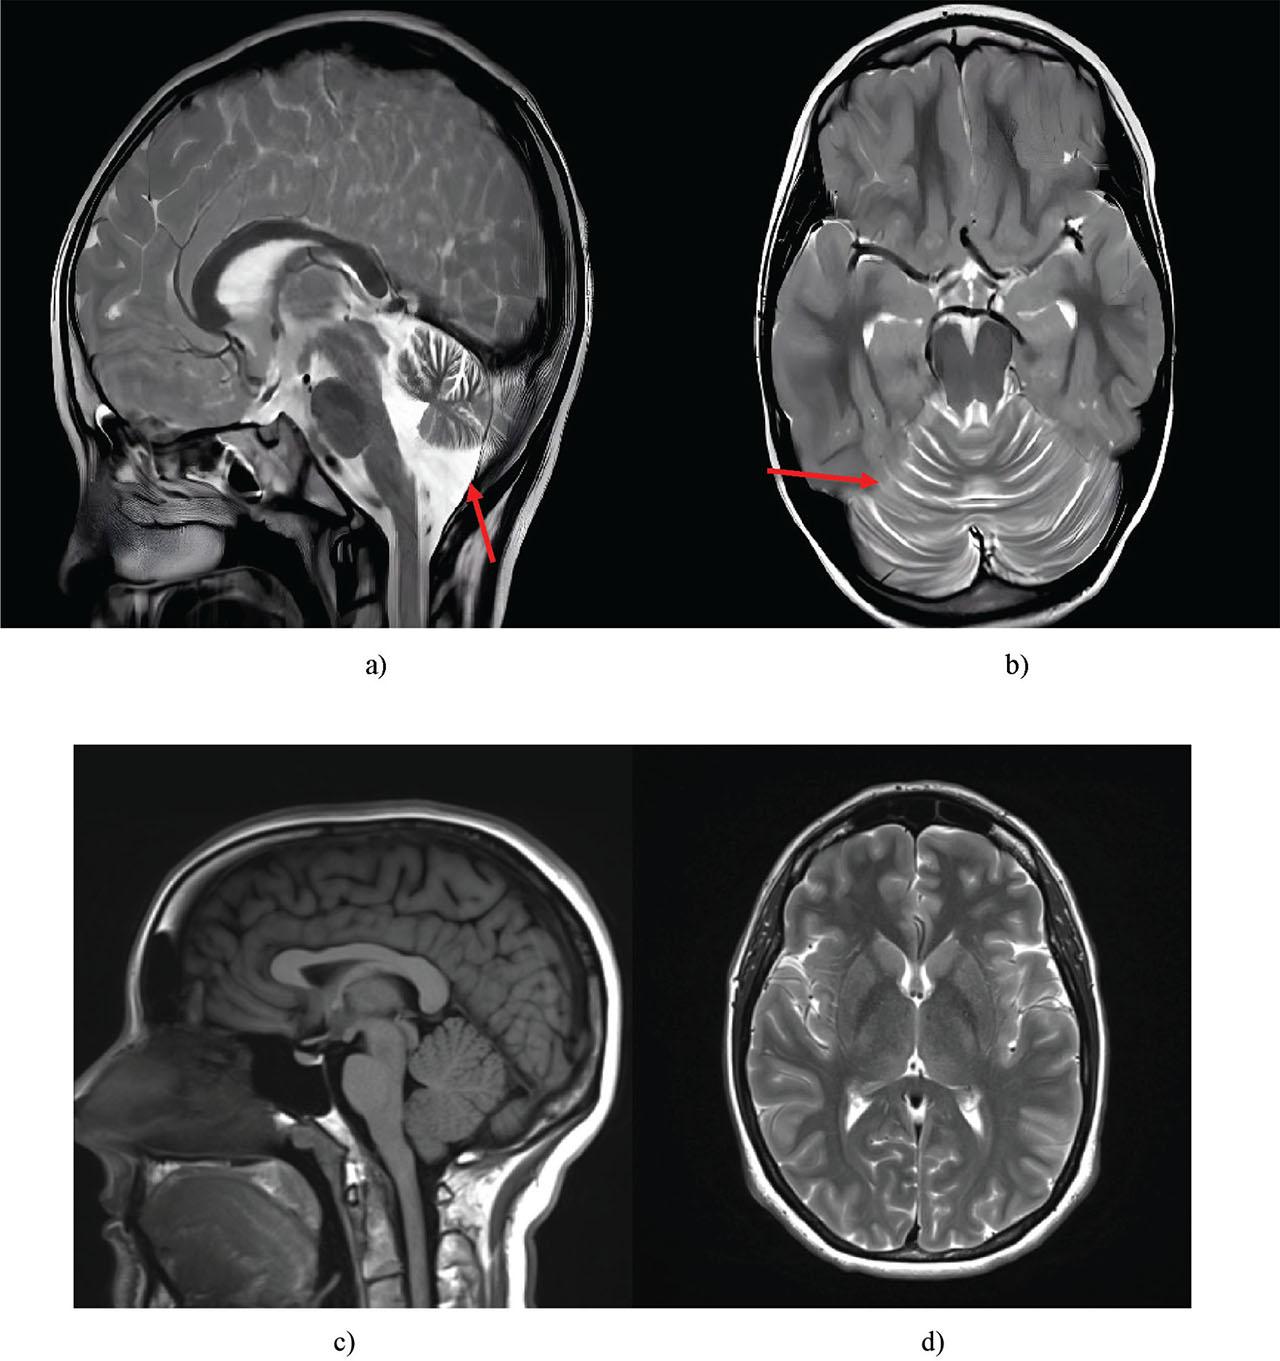

| Brain MRI | Identification of cerebellar atrophy, enlargement of the cisterna magna |